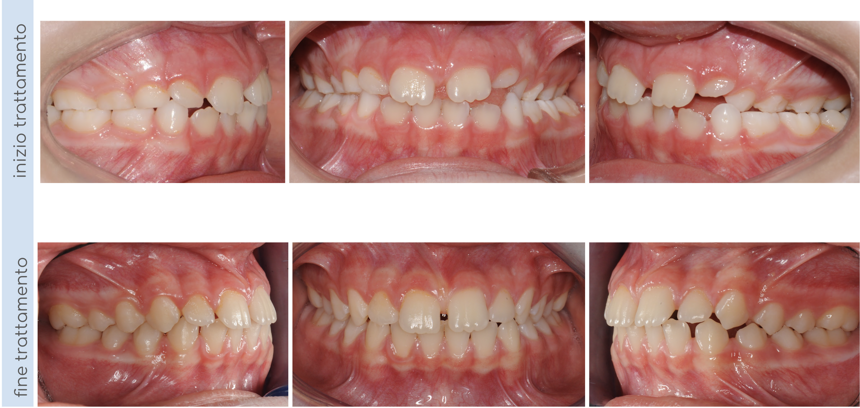

In questo caso, il paziente presentava un morso crociato posteriore a sinistra, intercettato precocemente e corretto in dentatura mista. Al termine della terapia intercettiva, una volta erotti tutti i denti permanenti, il nostro piccolo paziente ha iniziato una seconda fase di terapia con allineatori trasparenti per finalizzare il trattamento e allineare correttamente le arcate!